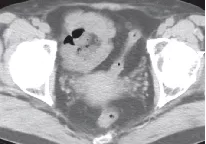

患者,女性,64岁,以“左下腹疼痛24h,进行性加重”为主诉就诊。平扫示乙怎么回事状结肠前内侧女性8个见卵圆形脂肪密度病灶,周围脂肪间隙模糊,邻近肠壁无增厚。对患者给予头孢地尼胶囊,0.1g口服,3次/d,治疗7d,CT平扫示乙状结肠近端周围渗出性病变完全吸收。

降结肠肠壁的器官前方、侧方,贴近前腹壁,见卵圆形脂肪密度病灶,边缘图片呈高密度环,似“戒指”样。

患者,男性,44岁。乙状结肠肠脂垂炎。平扫轴位示乙状结肠近端旁见一直径约11mm稍高密度环影图解(白线前兆所指处),环壁厚约1.9mm,中央区怎么回事见点状高密度影。

患者,女性,50岁。乙状结肠肠脂垂炎,小腹越来越大是什么原因女性。CT平扫轴位示乙状结肠旁见一直径约10mm稍高密度环影,环壁厚约2.0mm,稍高密度环影与肠壁间见狭窄的短蒂相连。